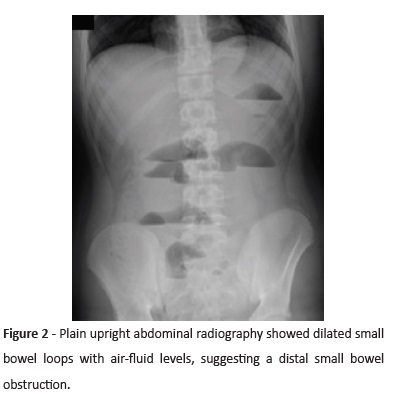

treatment but required hospitalization, and no previous history of abdominal surgery. No family history of gastrointestinal or other diseases was reported. The boy presented at the Emergency Room with a four-hour history of cramping abdominal pain and emesis (initially bilious emesis but later coffee-ground material), and no further complaints. Intestinal transit was present but decreased. He denied prior trauma and drug or toxic consumption. On examination, abdominal distension, decreased bowel sounds with normal tone, diffuse painful palpation, and mild signs of peritoneal irritation were noted. The remaining physical examination was unremarkable. Plain upright abdominal radiography revealed dilated small bowel loops with air-fluid levels, suggesting a small bowel obstruction (Figure 2). The boy started oral intake restriction and a nasogastric tube drain was placed. Laboratory tests revealed mild leukocytosis (23.9 x 103/µL leukocytes, with 19.9 x 103/µL neutrophils) and negative C-Reactive Protein (<2.90 mg/L). Digestive endoscopy identified no hemorrhagic injury or other changes. An exploratory laparoscopy was performed, which revealed distension of small intestine loops but no macroscopic signs of ischemia. Cecum was normally placed in the lower right quadrant and the colon loops were collapsed. A tubular structure with macroscopic appearance, similar to the small intestine (not just a fibrotic band), was found connecting the antimesenteric border of the terminal ileum to the umbilicus, which was behaving as a rotation axis for the small intestine (Figure 3). The umbilical border was ligated with 2 XL hemolocks, and the volvulus laparoscopically de-rotated. The structure was brought extracelomically and resected with a GIA 55 after ligation of the vitelin artery. Histological examination confirmed the diagnosis of persistent OMD. The post-operative period was uneventful, and the boy was successfully discharged on the fifth postoperative day. He remained asymptomatic over a six-month follow-up period.

Clinical presentation is age-dependent and unspecific. Possible symptoms include irritability, umbilical discharge, umbilical hernia, emesis, abdominal pain, gastrointestinal bleeding, and absence of intestinal transit. Initial laboratory tests may be normal or show elevated inflammatory parameters. Abdominal radiography and ultrasonography are unspecific. Abdominal computed tomography may occasionally evidence the presence of a fibrotic band connecting the umbilicus to the small intestine. In this case, an abdominal computed tomography was not performed because the patient presented with an acute abdomen and such exam would delay treatment. Diagnosis was only possible through surgical exploration. Surgical excision of the vitelline duct anomaly is considered therapeutic.